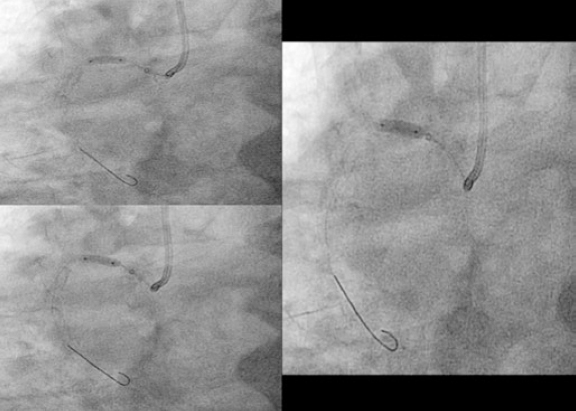

Afterwards we proceeded with the eventless advancement of a new zotarolimus-coated stent (Medtronic Resolute Onyx, 4 × 22 mm) towards the proximal segment by navigating inside the guiding catheter extension device (figure 3). This second stent was implanted and anchored to the previous one and adjusted to the ostium. It was dilated with high pressure with the delivery balloon including the visible segment protruding into the aorta in order to achieve the longitudinal shortening of the stent by overexpansion (figure 4).

Figure 3. Implantation of zotarolimus-coated stent in the proximal segment of right coronary artery.